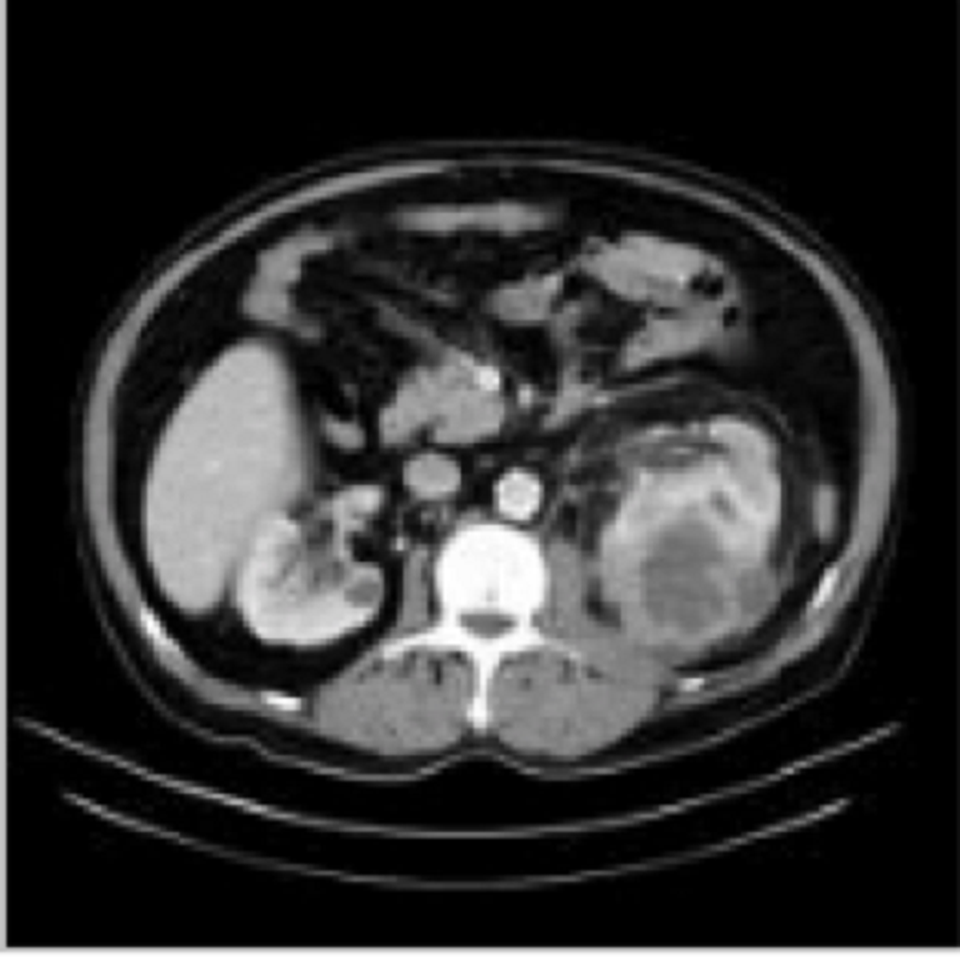

Kết quả CT-Scan bụng ghi nhận nhưng dấu hiệu bất thường ở thận của trẻ

Kết quả CT-scan cho thấy bệnh nhi có ổ áp xe thận trái, đây là một bệnh lý tương đối hiếm gặp ở trẻ em, nguy cơ nhiễm trùng huyết nặng hoặc phải phẫu thuật dẫn lưu khối áp xe nếu không được điều trị kịp thời. Ngay sau chẩn đoán, bác sĩ đã tiến hành điều trị tích cực cho bệnh nhi với kháng sinh mạnh. Sau hơn hai tuần, bệnh nhi hết sốt, sức khỏe bình phục, vùng hông lưng hầu như không còn đau. Kiểm tra trên siêu âm cho thấy khối áp xe đáp ứng giảm kích thước.